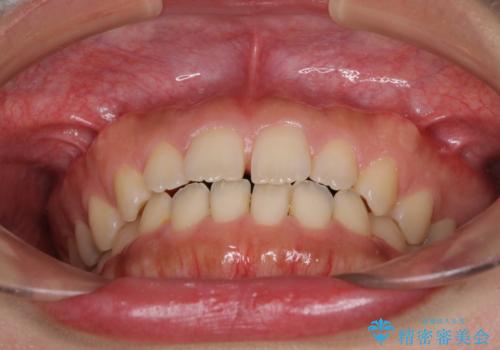

気になる隙間の再矯正 前歯をインビザライン・ライトで改善

- 後戻りによる上下前歯の隙間を気にして来院された患者様です。

歯列不正はそれほど大きくなかったため、インビザライン・ライトを用いて矯正治療を行うこととしました。

無理のないペースで治療を進め、9ヶ月で終えることができました。